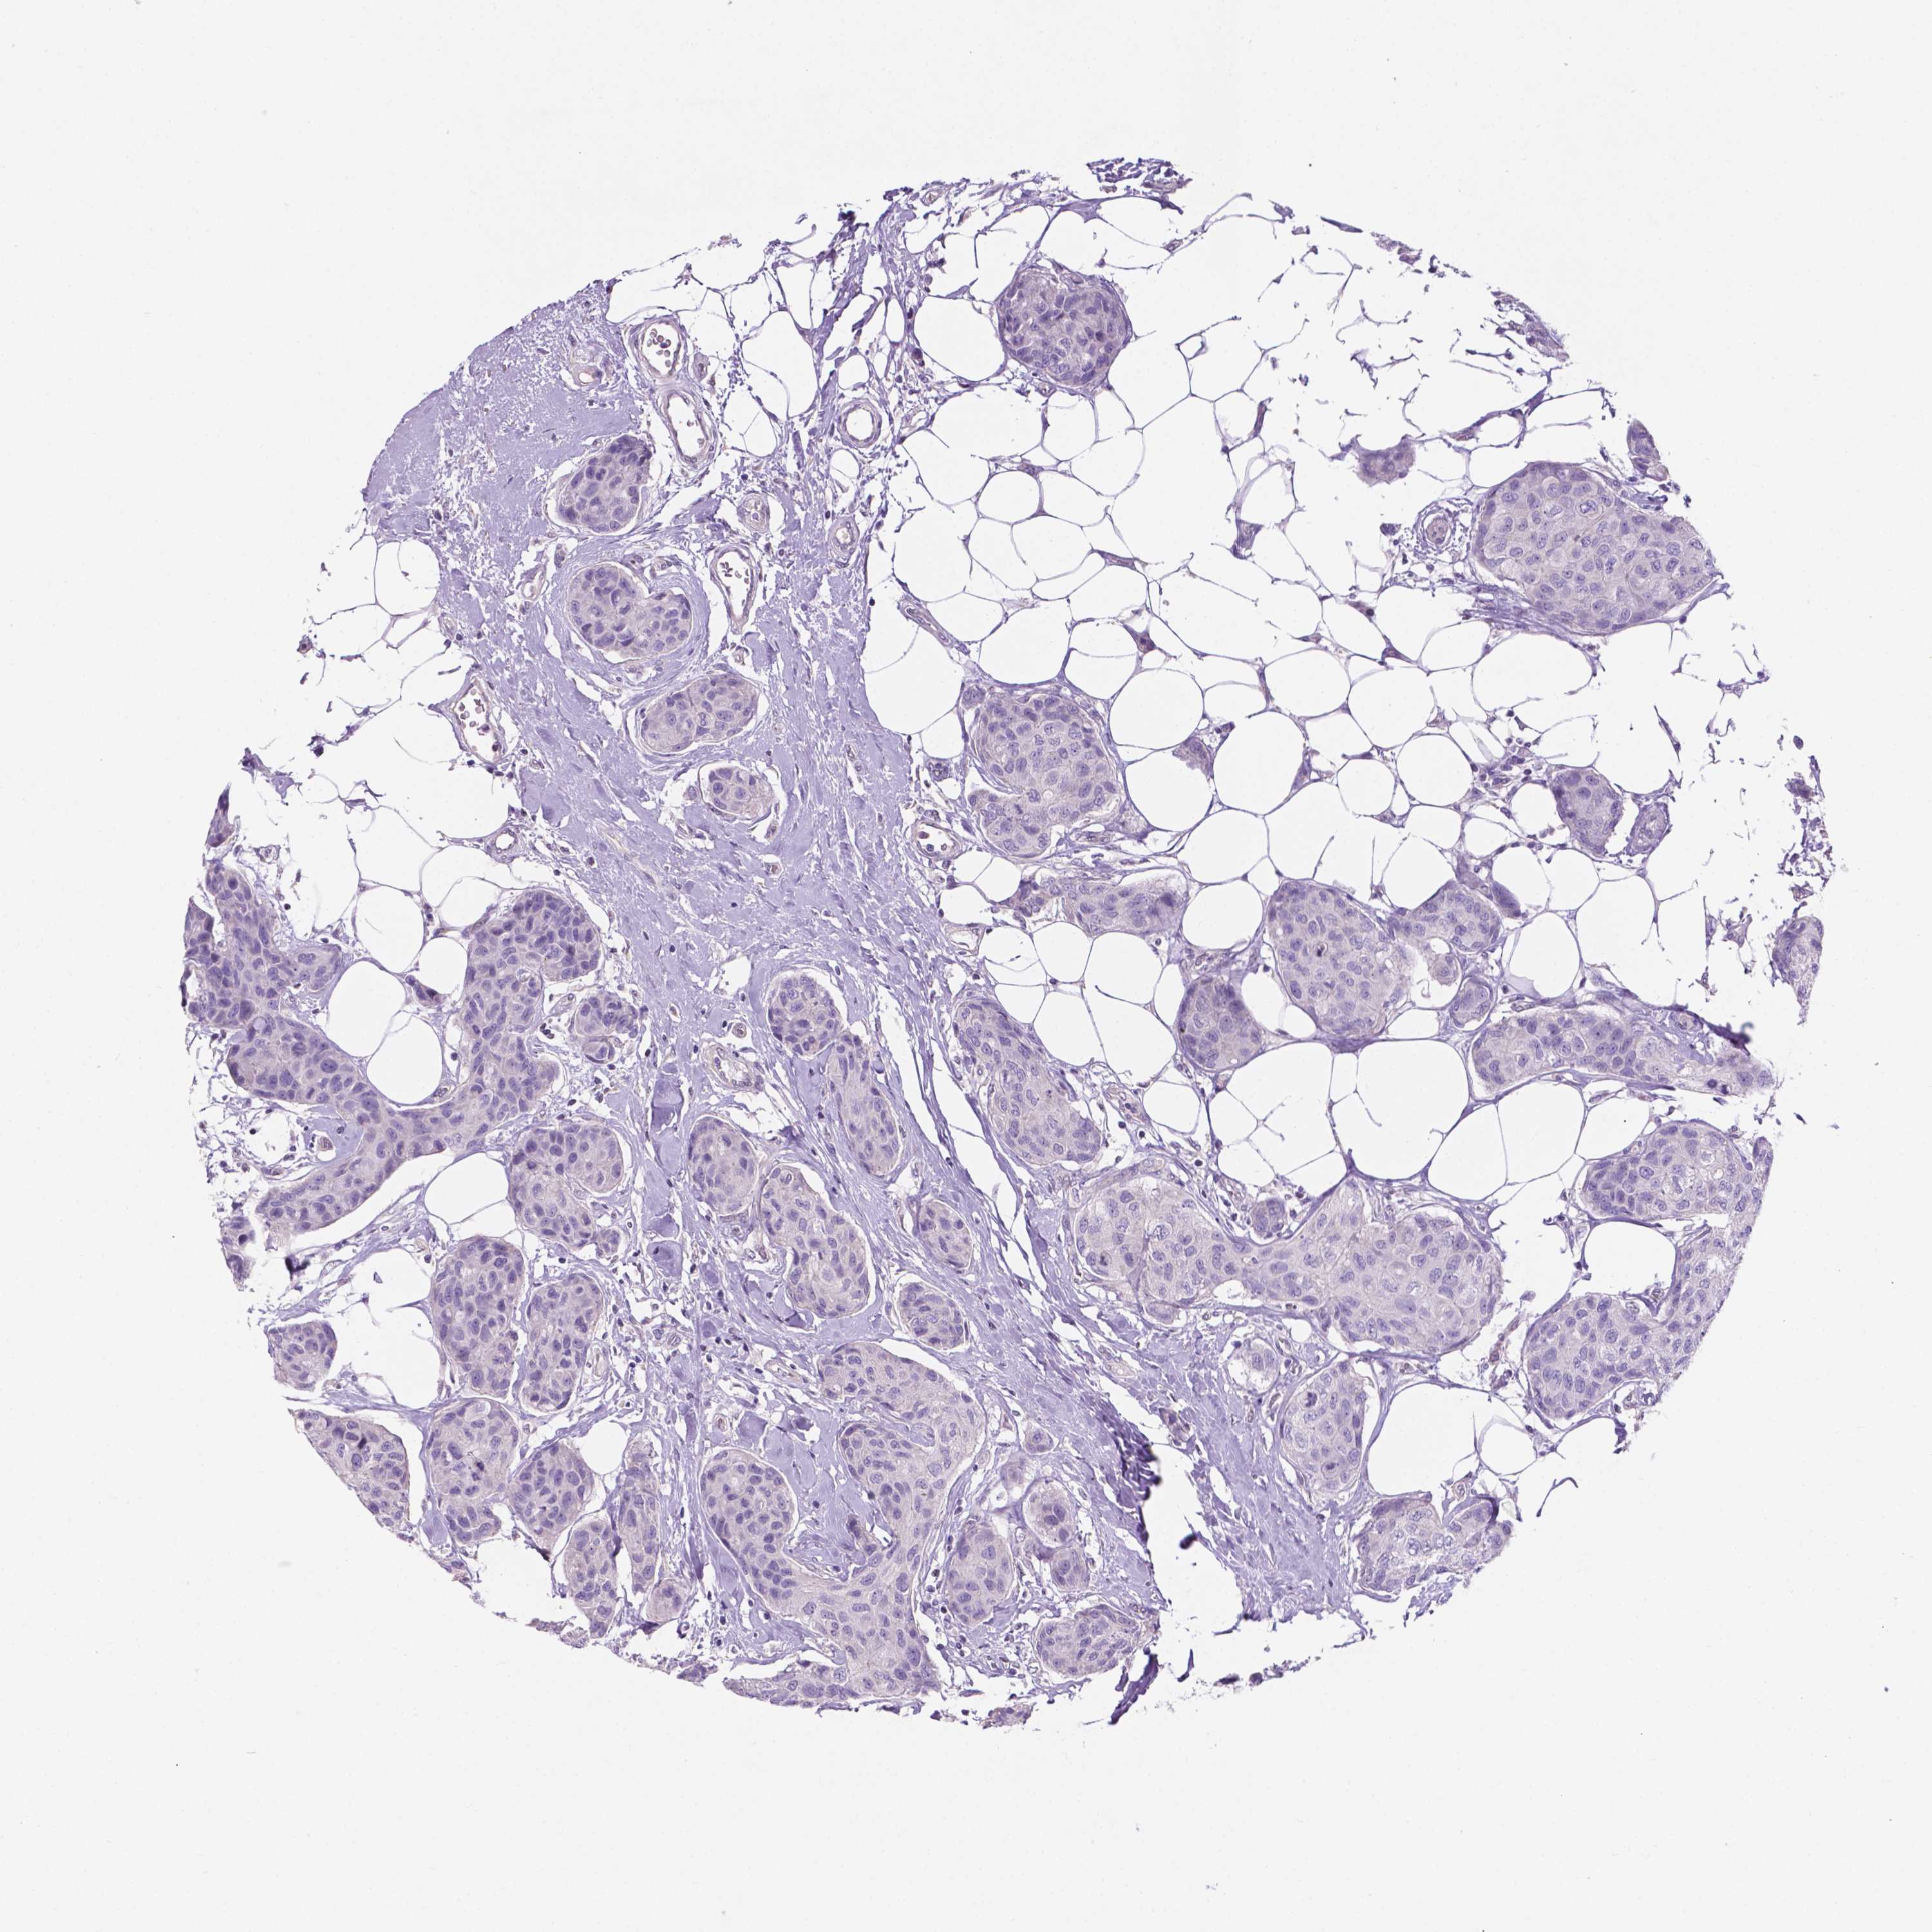

CANCER BREAST CANCER Show tissue menu

BRCA TCGA BRCA VALIDATION PROTEIN EXPRESSION

Breast cancer

Human cancer